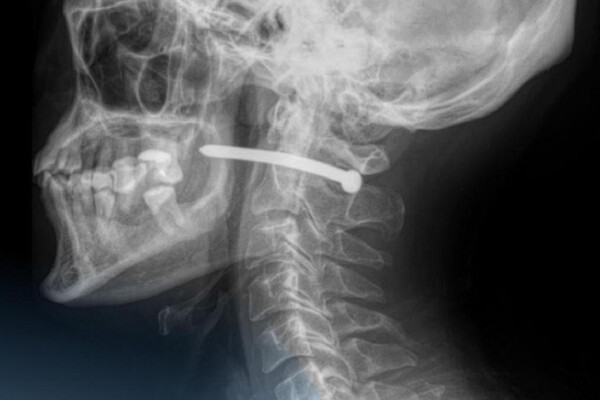

В Петропавловске 51-летний мужчина обратился в городскую больницу скорой помощи с ранением за ухом. Как выяснилось, во время ремонта он случайно получил травму — в него выстрелил гвоздь из пневматического пистолета.

Рентген показал, что металлический предмет прошел буквально в миллиметрах от шейного отдела позвоночника. Медики отметили, что мужчине невероятно повезло — жизненно важные органы и сосуды не были повреждены.

Хирурги извлекли гвоздь, тщательно обработали рану и наложили швы. После процедуры пациента отпустили домой с рекомендациями. Врачи напомнили, что любые травмы шеи представляют серьезную опасность, ведь в этой области проходят крупные артерии, нервы, дыхательные пути и спинной мозг.